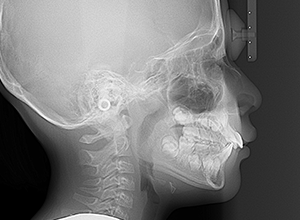

動的治療終了時

X-Ray

X-Ray所見

セファロ所見 SNAは84.3°、SNBは77.2°、ANBは7.1°とskeletal ClassⅡ、垂直的にはロウアングルの骨格形態をしていた。 上顎前歯は唇側傾斜を呈していた。

批評・予后 本来であれば永久歯歯列完成後に本格矯正治療を行って良い症例だが、患者さん(保護者)の強い希望から早期治療にて改善を行った症例である。バイオネーターを夜間就寝中に使用して咬合誘導を行った結果、前歯の前突感は解消され比較的緊密な咬合は得られたように思う。